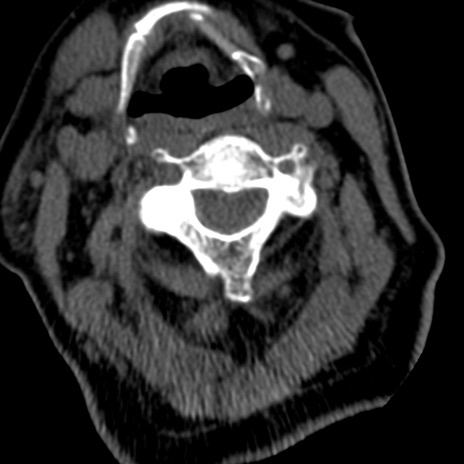

症例50 頚椎CT(横断像)

【症例】60歳代女性

【主訴】後頭部〜右後頸部にかけての痛み

【現病歴】本日飲食店でコーヒーを飲んでいたところ、突然後頭部〜右後頸部にかけて痛みが出現し、右上肢の感覚障害を伴ったため救急要請。

【身体所見】脳神経学的に明らかな異常所見を認めず。右上肢に軽度の感覚障害あり。

異常所見と診断は?

頚椎CT